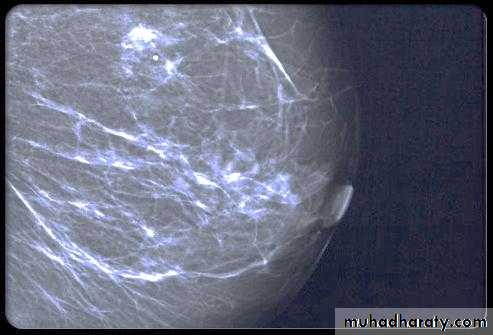

Micro calcifications

Micro calcifications are tiny specks of calcium in the breast. Micro calcifications seen on a mammogram are of more concern than macrocalcifications, but they do not always mean that cancer is present. The shape and layout of microcalcifications help the radiologist judge how likely it is that cancer is present.

In most cases, the presence of microcalcifications does not mean a biopsy is needed. But if the microcalcifications have a suspicious look and pattern, a biopsy will be recommended. (During a biopsy, the doctor removes a small piece of the suspicious area to be looked at under a microscope. A biopsy is the only way to tell if cancer is really present.)